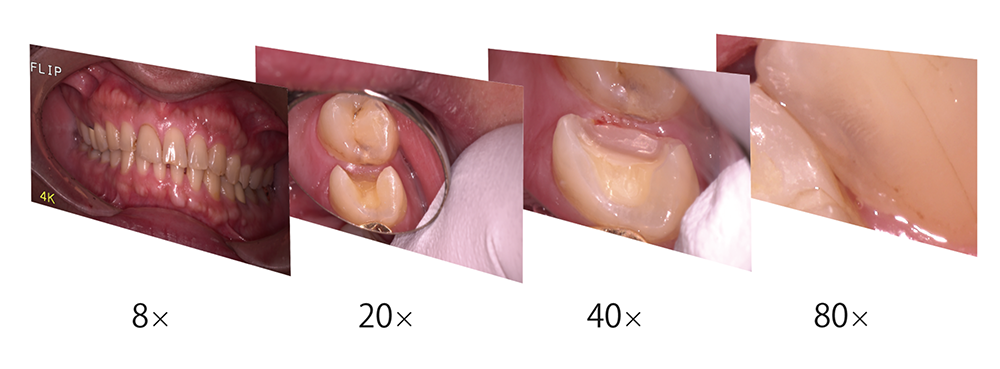

口腔内カメラと顕微鏡を兼ね備えたデジタルマイクロスコープ

ソヤ歯科では、精度の高い治療をご提供するため高倍率のマイクロスコープ「ネクストビジョン」を完備しております。肉眼の最大80倍まで視野を拡大できる顕微鏡の機能と口腔内カメラを搭載した精密機器です。拡大視野によって適切な処置が可能となり、「審美性の向上」をはじめ、お口の長期的な健康維持が実現します。同じ箇所を何度も治療されている方やできるだけ天然歯を維持したい方はぜひ、マイクロスコープによる精密治療をご検討ください。

治療患部の拡大映像をモニターで確認しながら、精度の高い処置が行えます。歯面や歯間、根管内部の状態を正確に捉えることができるため、さまざまな症状に対して的確な治療がご提供可能です。

高倍率マイクロスコープ「ネクストビジョン」を通して見える世界

-